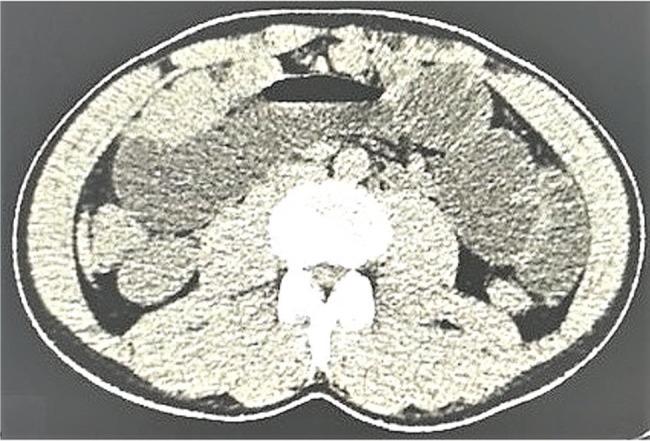

Histopathology is the 'gold standard' for diagnosing renal cell carcinoma but is limited by sample size. Contrast-enhanced ultrasound can differentiate malignant and benign lesions, but the Chinese guidelines on the management of renal cell carcinoma do not include this method. The purpose of this study was to compare the diagnostic parameters of contrast-enhanced ultrasound against those of contrast-enhanced computed tomography for detecting kidney lesions, with histopathology considered the reference standard.

Patients with suspected kidney lesions from prior grayscale ultrasonography and computed tomography were included in the analysis (n=191). The contrast-enhanced ultrasound, contrast-enhanced computed tomography, and histopathology data were collected and analyzed. A solid, enhanced mass was considered a malignant lesion, and an unenhanced mass or cyst was considered a benign lesion. The Bosniak criteria were used to characterize the lesions.

Contrast-enhanced ultrasound and contrast-enhanced computed tomography both detected that 151 patients had malignant tumors and 40 patients had benign tumors. No significant differences in the tumors and their subtypes were reported between contrast-enhanced ultrasound and histopathology (p=0.804). Chromophobe renal cell carcinoma was detected through contrast-enhanced computed tomography (n=1), but no such finding was reported by contrast-enhanced ultrasound. A total of 35 cases of papillary renal cell carcinoma were reported through contrast-enhanced ultrasound while 32 were reported through histopathology.

Contrast-enhanced ultrasound might be safe and as accurate as histopathology in diagnosing kidney lesions, especially renal cell carcinoma. Additionally, this study provides additional information over histopathology and has an excellent safety profile.